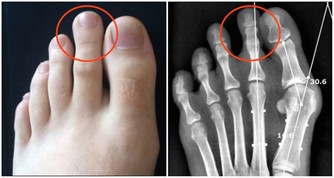

局部多汗症

局部多汗症是指平時全身汗不多,只是在身體的某個特定部位出汗較多,例如腋下、手心、腳心等。腎氣虛、精神壓抑等都會導致局部多汗症。